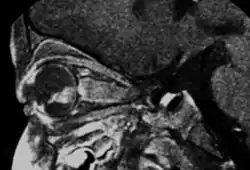

- MRI: assessment of local extension to optic nerve, anterior chamber, and orbital fat. Slightly hyperintense on T1, hypointense on T2. Also to rule out trilateral retinoblastoma